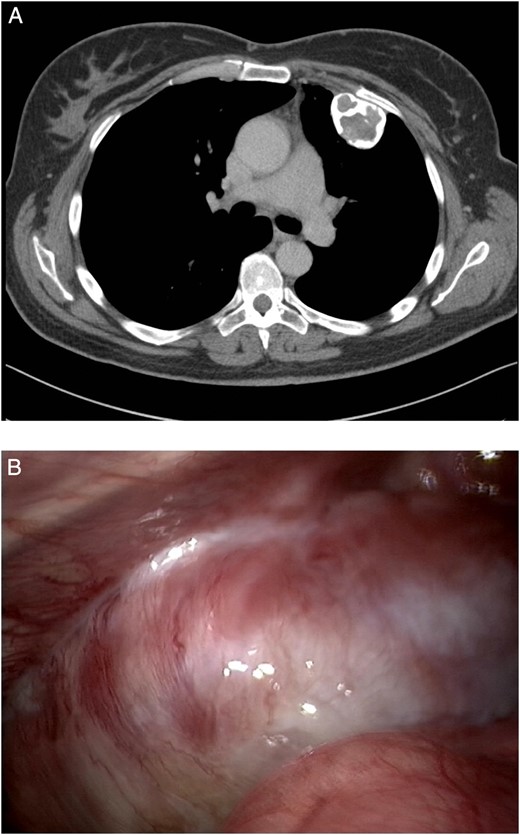

Additional imaging was obtained by a chest CT scan, which showed a calcified tumour on the left thoracic wall growing from the second rib with slight impression of the lung with a maximal diameter of 4.7 cm (Fig. 1A). Differential diagnostic consideration included chondroma, FD or low-grade sarcoma. No other lesions in the lung or chest wall were identified.

(A) A calcified tumour on the left chest wall growing from the second rib with slight impression of the lung with a maximal diameter of 4.7 cm. (B) Bony tumour originating from the left second and third rib, with some pleural adhesions.

With no other lesions explaining the chronic cough, resection through video-assisted thoracoscopy (VATS) was planned in multidisciplinary consultation. During VATS, a bony tumour was found originating from the left second and third rib, with some pleural adhesions (Fig. 1B). The procedure was converted to thoracotomy to perform wide resection of the thoracic wall (Fig. 2).